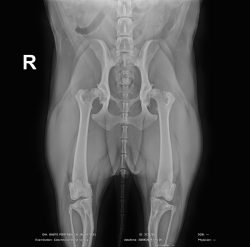

Labrador Retriever de 1 año que acude a consulta para descartar displasia de cadera. Los tutores refieren que “corre como un conejo” y se fatiga rápido durante el juego. No presenta antecedentes relevantes y la exploración física es normal. En la exploración ortopédica se evidencia molestia a la manipulación de la cadera, pese a tener buen rango de movimiento y signo de Ortolani positivo. Se obtiene la radiografía adjunta (Figura 3).

Pregunta: ¿Cuáles son las características clínicas iniciales y los signos radiológicos tempranos que debemos buscar en un perro joven con sospecha de displasia de cadera?

Clínicamente, los signos tempranos incluyen marcha en “salto de conejo”, intolerancia al ejercicio acompañado de atrofia muscular y molestia/dolor a la manipulación. Radiológicamente, los hallazgos iniciales pueden ser sutiles: subluxación leve, cobertura acetabular insuficiente, aumento del espacio articular, cuello femoral algo aplanado y borde acetabular dorsal reducido. En fases muy tempranas puede no haber cambios degenerativos evidentes, pero la relación cabeza–acetábulo puede mostrar laxitud que es clave en el diagnóstico precoz.